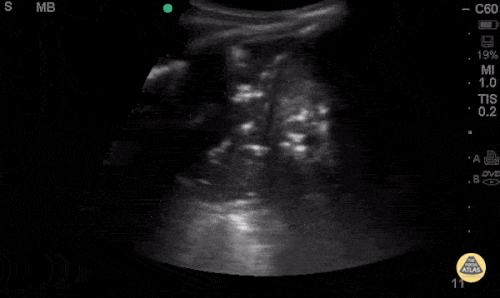

Hydronephrosis

Examples: http://www.thepocusatlas.com/hydro-and-obstruction/